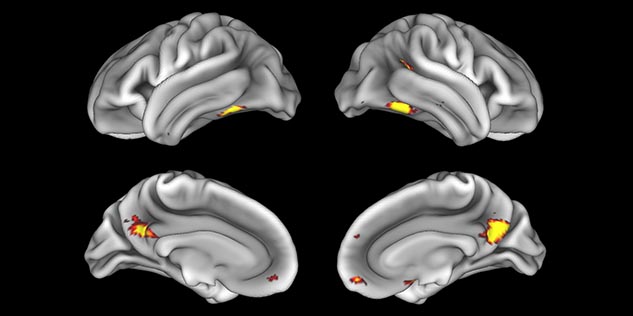

Imaging was performed using Ingenia 3T CX with a 32ch dS Head coil, TR 1.6 sec, TE 35 ms, voxel size 3.1 x 3.1 x 3.1 mm, 46 slices and Multiband SENSE factor 2. Image provided by Dr. Gispert

Default mode network as discovered by resting state fMRI in one participant of the ALFA cohort [7]. rs-fMRI allows us to find networks of brain regions with highly correlated activity and sustaining distinct brain functions. The default mode network (in warm color scale) is active when the brain is focused on introspective thinking and has been shown to be altered in Alzheimer’s. Interestingly, brain areas of this network are known to show abnormal levels of one of the pathological hallmarks of Alzheimer’s (b-amyloid deposition) in preclinical stages. We want to better understand the alterations of these brain networks in preclinical stages of Alzheimer's and explore their potential use as biomarkers.